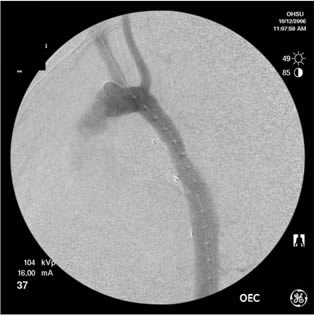

THORACIC AORTIC SYNDROMES Traumatic Aortic Rupture, Aortic Aneurysm, Aortic Dissection, Intramural Hematoma, and Penetrating Atherosclerotic Ulcer Stephen Ledbetter, MD, Jeffrey L. Stuk, DO, and John A. Kaufman, MD Catheter angiography has traditionally been the ... Get Doc

Repair of penetrating thoracic aortic ulcers has not pre-viously been reported. 4,5 We present two patients with ruptured penetrating ulcers of the thoracic aorta who which a penetrating ulcer of the mid-descending aorta was also (Fig 1A) revealed. ... Document Viewer

Stent Graft In Treatment Of Penetrating Thoracic Aortic Ulcer

Figure 1 A, Contrast-enhanced computed tomographic scan at level of descending aorta demonstrates wide neck posterior penetrating ulcer (arrow). ... Doc Viewer